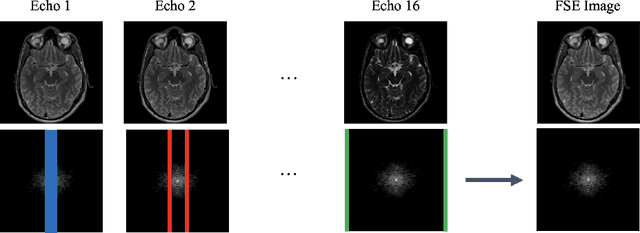

Abstract:Magnetic Resonance Imaging (MRI) is a widely used medical imaging modality boasting great soft tissue contrast without ionizing radiation, but unfortunately suffers from long acquisition times. Long scan times can lead to motion artifacts, for example due to bulk patient motion such as head movement and periodic motion produced by the heart or lungs. Motion artifacts can degrade image quality and in some cases render the scans nondiagnostic. To combat this problem, prospective and retrospective motion correction techniques have been introduced. More recently, data driven methods using deep neural networks have been proposed. As a large number of publicly available MRI datasets are based on Fast Spin Echo (FSE) sequences, methods that use them for training should incorporate the correct FSE acquisition dynamics. Unfortunately, when simulating training data, many approaches fail to generate accurate motion-corrupt images by neglecting the effects of the temporal ordering of the k-space lines as well as neglecting the signal decay throughout the FSE echo train. In this work, we highlight this consequence and demonstrate a training method which correctly simulates the data acquisition process of FSE sequences with higher fidelity by including sample ordering and signal decay dynamics. Through numerical experiments, we show that accounting for the FSE acquisition leads to better motion correction performance during inference.